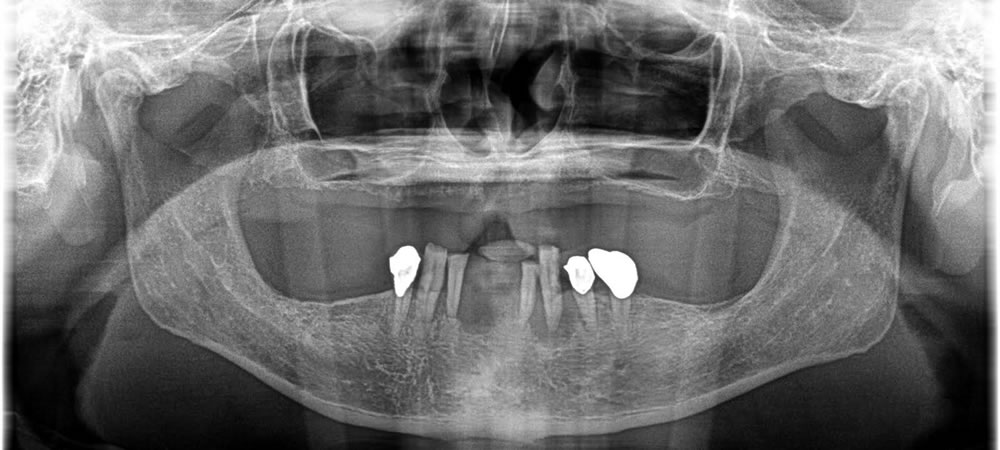

入れ歯とオールオン8による全顎治療の症例

年齢

50代

性別

男性

症例を見る